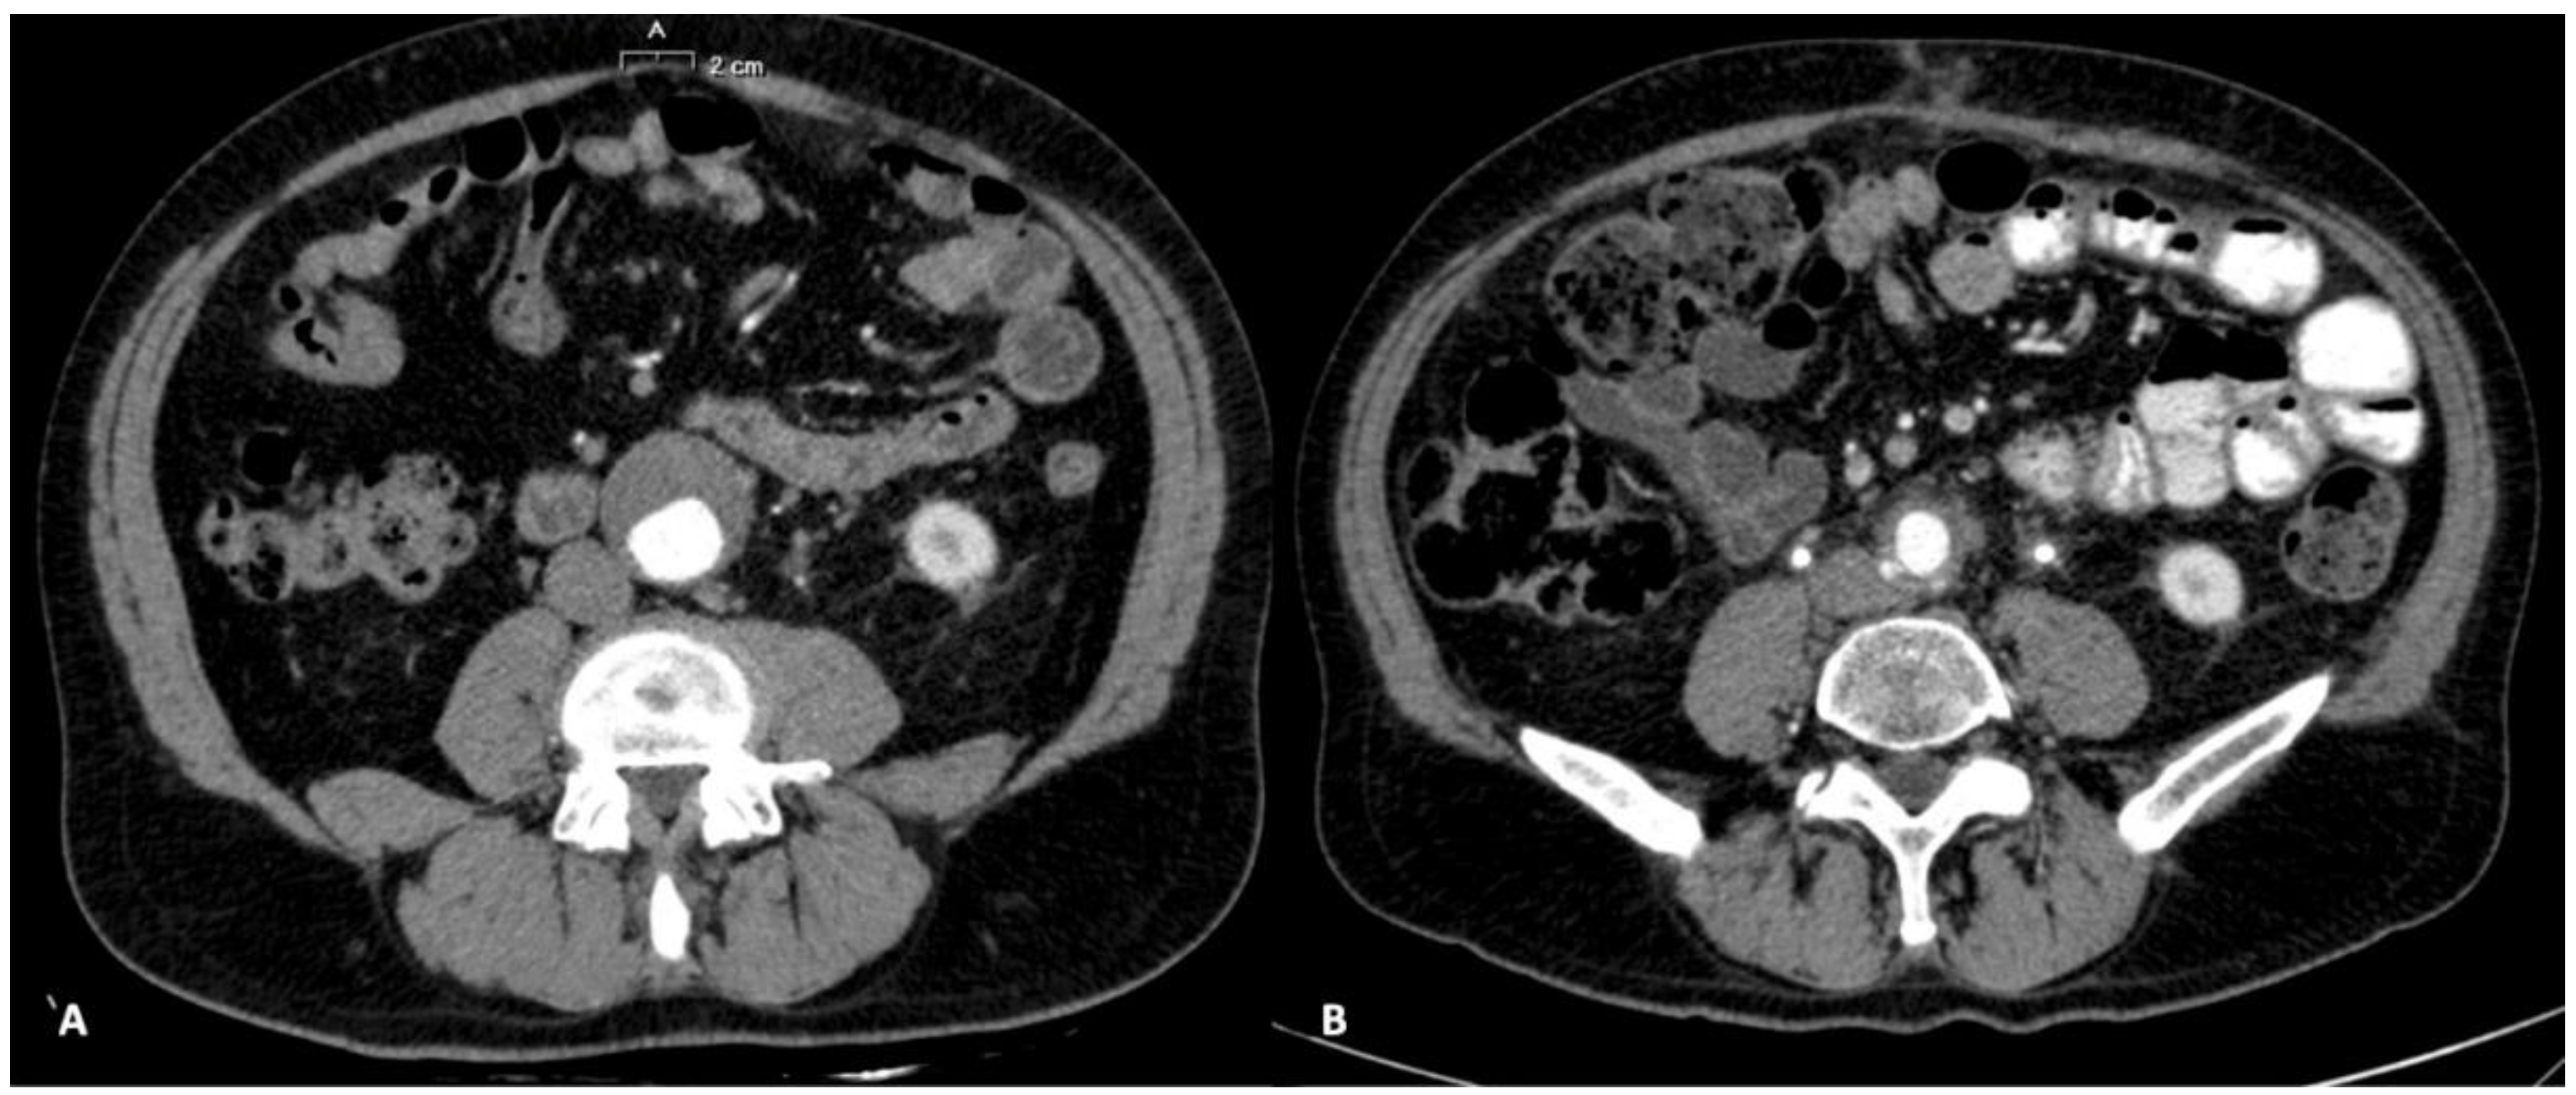

2. Case Report